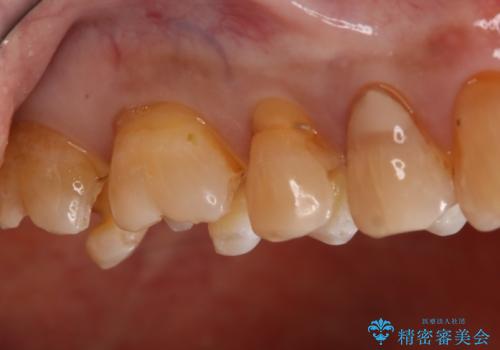

- かなり昔に入れた銀歯の部分のチェックをご希望でご来院されました。

上下ともに銀歯が多く入っており、その下に虫歯が疑われる状態でした。

詰め物の大きさや虫歯の状態から個々に材料と治療範囲を決定し治療に入りました。